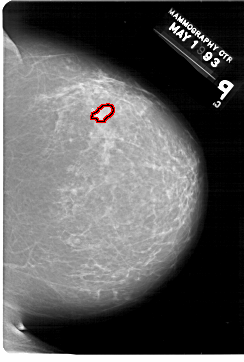

A_1421_1.RIGHT_MLO

RIGHT_MLO LINES 6871 PIXELS_PER_LINE 5251 BITS_PER_PIXEL 12 RESOLUTION 43.5 OVERLAY

FILE: A_1421_1.RIGHT_MLO.OVERLAY

TOTAL_ABNORMALITIES 1

ABNORMALITY 1

LESION_TYPE MASS SHAPE IRREGULAR MARGINS ILL_DEFINED

ASSESSMENT 4

SUBTLETY 2

PATHOLOGY BENIGN

TOTAL_OUTLINES 1

BOUNDARY